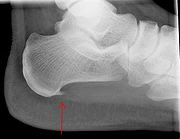

A dropped metatarsal is caused by the misalignment of the arches and the bone structure can no longer support itself and the bone structure collapses. Heel Spurs

Accumulation of calcium in the heel area is caused by the tearing of the fascia from the heel (Plantar Fasciitis). The body can send calcium to the area of the tear to work like glue to help prevent more tearing.| Heel spur Photo credit: Wikipedia |

The heel spur don’t usually hurt. The discomfort or pain is caused by the inflammation of the microscopic tearing. This can come and go and last for years. Sometimes a small hook shape can be on the top of the spur.